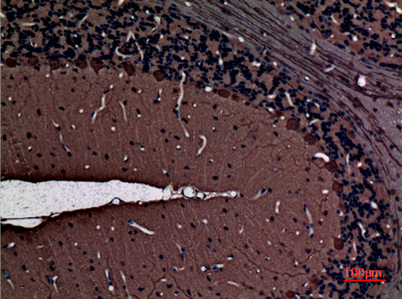

Dilutions: Western Blot: 1/500 - 1/2000. IHC-p: 1:100-300 ELISA: 1/20000. Not yet tested in other applications.

Background: Protein kinase C (PKC) is a family of serine- and threonine-specific protein kinases that can be activated by calcium and second messenger diacylglycerol. PKC family members phosphorylate a wide variety of protein targets and are known to be involved in diverse cellular signaling pathways. PKC also serve as major receptors for phorbol esters, a class of tumor promoters. Each member of the PKC family has a specific expression profile and is believed to play distinct roles in cells. The protein encoded by this gene is one of the PKC family members. This protein kinase is expressed solely in the brain and spinal cord and its localization is restricted to neurons. It has been demonstrated that several neuronal functions, including long term potentiation (LTP) and long term depression (LTD), specifically require this kinase. Knockout studies in mice also suggest that this kinase may be involved in neurop